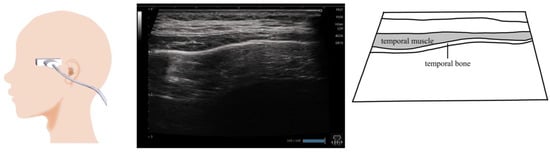

10. Temporalis Muscle (Figure 9)

- Watanabe, M.; Hironaka, S.; Utsumi, A.; Murata, N.; Mukai, Y. The standardized method for ultrasound imaging of oropharyngeal on swallowing. J. Jpn. Soc. Disabil. Oral. Health 2011, 32, 19–28. (In Japanese) [Google Scholar]